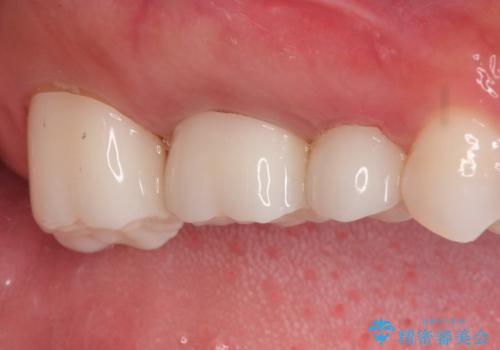

保険で治療した歯が欠けた。オールセラミッククラウンによる修復

- 以前、他院で保険治療の被せ物を入れた歯が欠けてしまったことを主訴に来院されました。

その他の歯も適合が悪く治療が必要でしたので、3歯まとめて治療を行いました。

- 21万円費用は治療当時の料金となります